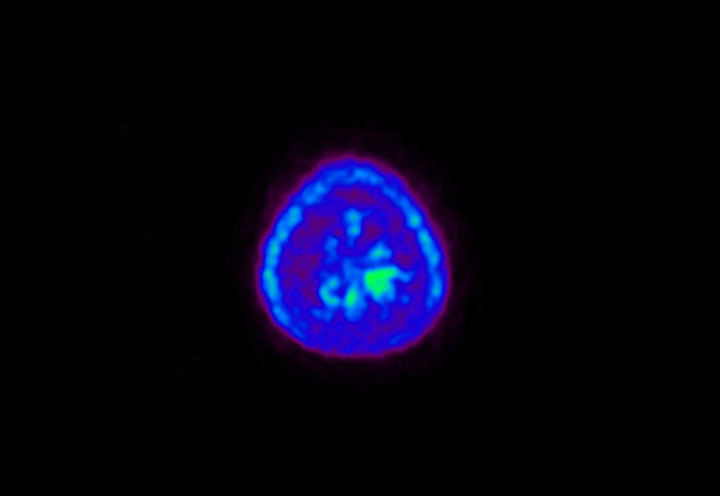

Head / Case5 : Amyloid

Sagittal

Courtesy : Kindai University Hospital

- Imaging protocol

- Injected dose: 4.27 MBq/kg, 18F-Flutemetamol

- Uptake time: 99 minutes

- Scan time: 20 minutes